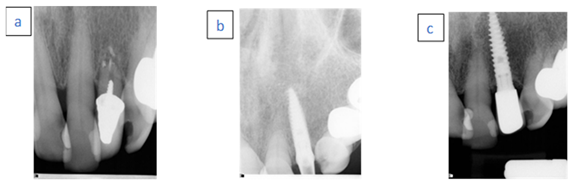

- A 46-year-old female.

- Nonsmoker with generalized aggressive periodontitis.

- Case 3 (a) Hopeless left central incisor due to advanced bone loss.

- Case 3 (b) Immediate implant placement with temporary abutment. Radiopaque material demonstrated above the implant neck.

- Case 3 (c) Follow-up examination after 96 months.

- A 76-year-old female.

- Nonsmoker with chronic advanced periodontitis.

- Case 4 (a) Hopeless left lateral first incisor due to external root resorption.

- Case 4 (b) Immediate implant placement with temporary abutment.

- Case 4 (c) Follow-up examination after 24 months.